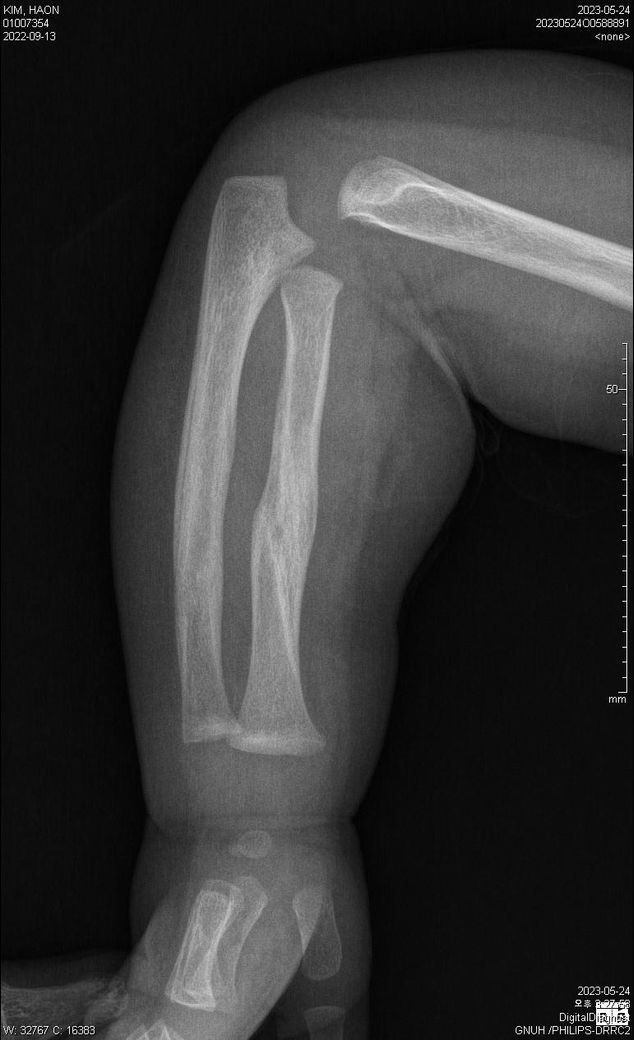

5월 24일 및 7월 11일 X-ray 상의 골절 치유 질의

첨부된 파일에 기재된 사실과 같이 23년 5월 24일 촬영된 양팔 X선 2장과

23년 7월 11일 촬영된 양팔 X선 2장입니다.

양팔이 골절이 되었었는데요,

1) 5월 24일 X선이 가골형성 시기인지, 재형성(리모델링) 시기인지 궁금합니다.

3) 5월 24일 X선에 비해 7월 11일 X선은 또한 어떤 치료단계인지 문의드리고자 합니다.

4) 종합하자면 3월 초~ 중순에 골절이 일어났다고 보는게 타당한지?

• 1번 째 사진